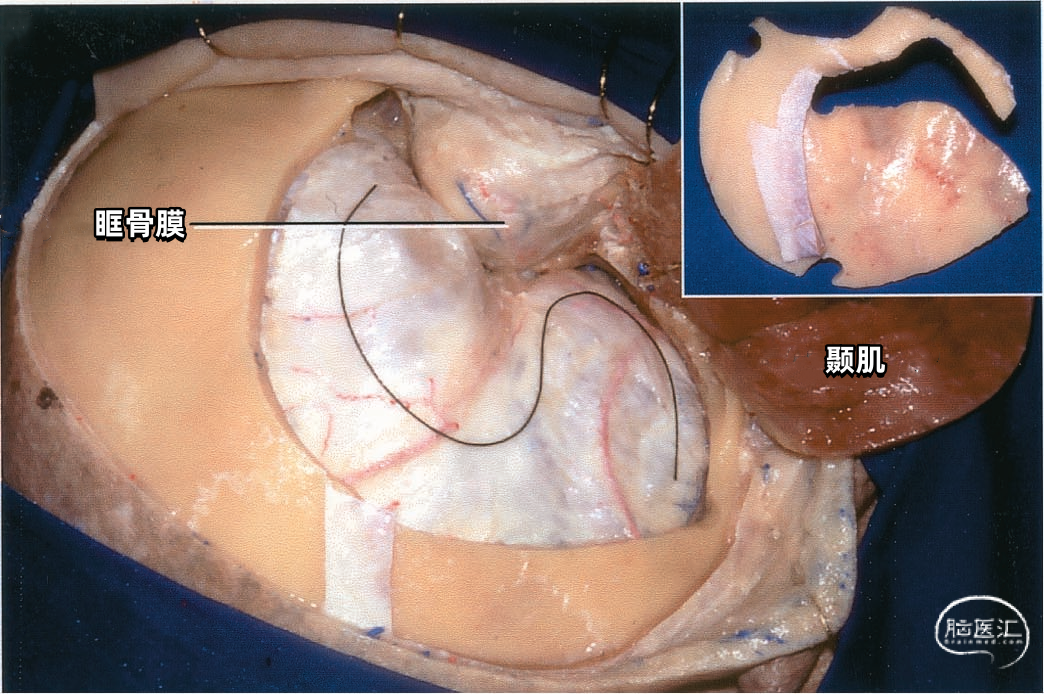

下图示右侧眶颧开颅。颞肌被翻向下方,掀起骨瓣,实线标出硬膜切口。插图显示一块眶颧骨瓣。

下图示切开硬膜,暴露一支粗大的外侧裂浅静脉,汇入蝶骨嵴的蝶顶窦。

下图示打开外侧裂,牵拉外侧裂浅静脉显露颈内动脉和大脑中动脉。

下图示另一例眶颧开颅。此标本的外侧裂浅静脉的前段缺如,外侧裂后半部的静脉引流注入经过额叶和颞叶的静脉。